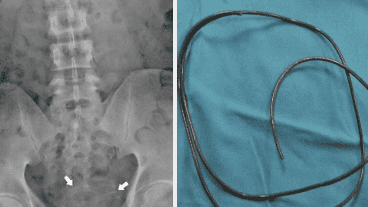

Los médicos lo describieron como "alojado en la vejiga". Le hicieron una radiografía para ver qué tan adentro de su cuerpo y cuánto daño había causado. Era 'visible y rápidamente identificado'.

El cable, que tenía alrededor de 3 mm de ancho, estaba enrollado pero, afortunadamente para él, no se había adherido a la pared de la vejiga.  Si se hubiera alojado, los urólogos afirman que podría haber causado un agujero que necesitaba cirugía para repararlo. Los médicos lo sacaron con unas pinzas, aunque no está claro si quedó algo del cable colgando para agarrarlo. El hombre pasó la noche en el hospital para ver si necesitaba más tratamiento. Fue dado de alta al día siguiente.